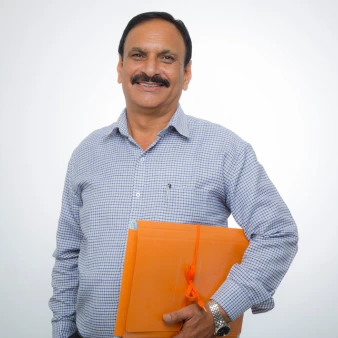

Dr. Sujit Nanda

Dr. Sujit Nanda is an MBBS, MD (Medicine), DM (Nephrology) specialist renowned for expertise in diagnosing and managing complex kidney-related conditions. With a strong background in renal medicine, Dr. Sujit Nanda offers cutting-edge treatment for patients with chronic kidney disease, dialysis needs, hypertension, and renal transplantation.

Combining medical precision with a compassionate approach, Dr. Sujit Nanda is committed to ensuring comprehensive kidney health and improving the quality of life for every patient.

Expertise in:

- Chronic Kidney Disease (CKD) management

- Dialysis (Hemodialysis & Peritoneal Dialysis)

- Kidney Stone Treatment

- Kidney Transplant evaluation and follow-up

- Hypertension & Renal Care

- Diabetic Kidney Care